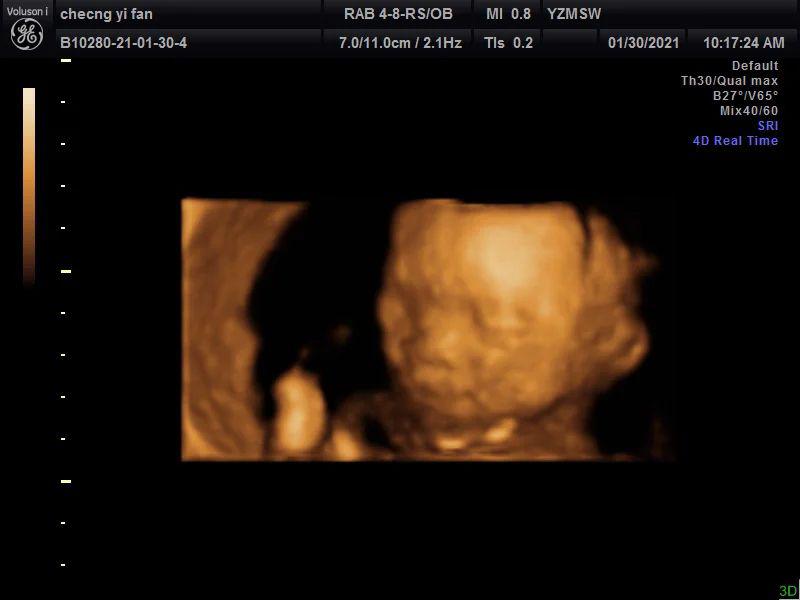

第二天四维是孕23周+4天,约了一个私立医院,主要是可以保存宝宝的照片和视频,于是就去了,这次是早上,宝宝非常配合(图三到图七)!脸和脚,小拳头,都拍的特别清楚,医生说宝宝很好看,尖尖的下巴,鼻梁好好的,眼睛也很大,到最后手放在脸上,还对我比了个✌️嘻嘻嘻,希望四维照片和宝宝出生照像一些~